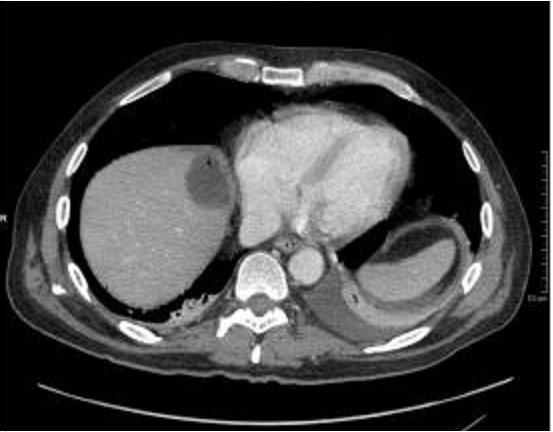

Image TDM du foie en coupe

axiale ( avec contrast iode intra veineuse ) . |

|

axiale a travers la vesicule biliaire ( avec

contrast ) . Veine porte , vesicule biliaire sont en

voyait |